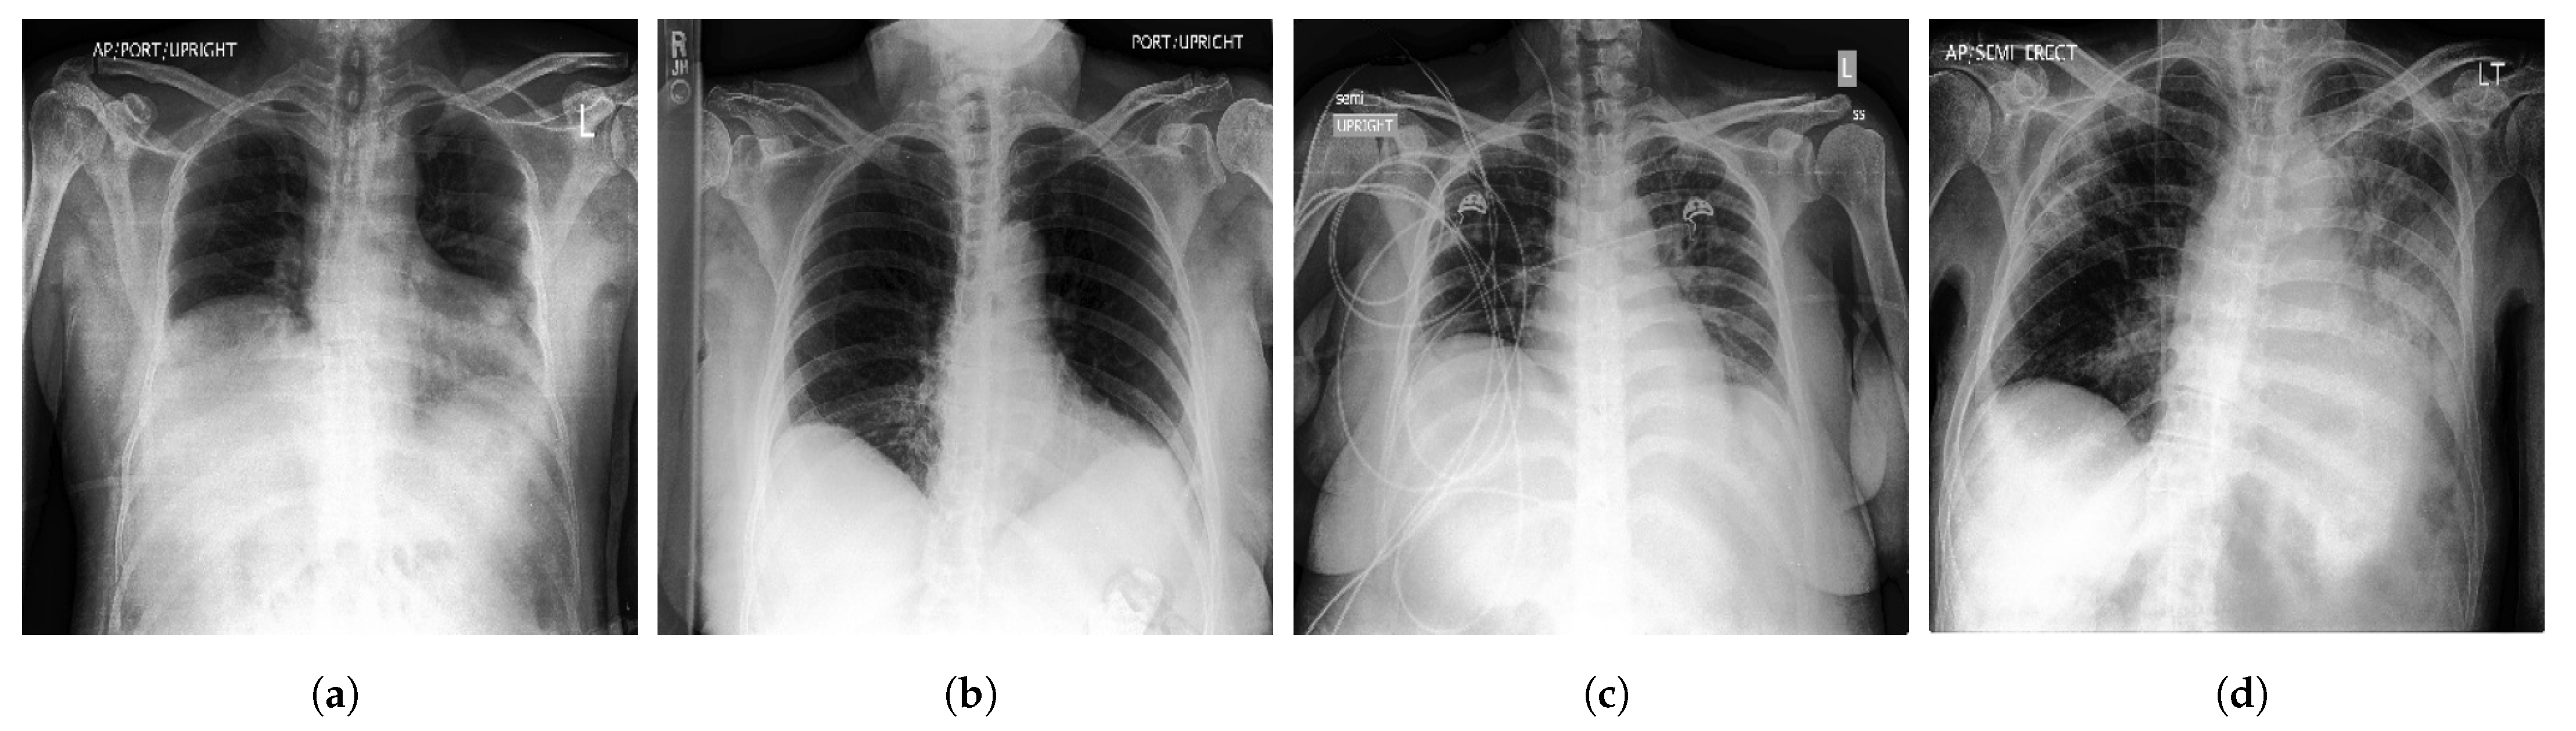

- VinDr-CXR [48] is a public CXR dataset with radiologist-generated annotations. It consists of 18,000 CXR images that come with the location and the classification of the chest diseases. This dataset was collected from two of the biggest hospitals in Vietnam that are Hospital H108 and the HMUH (Hanoi Medical University Hospital) [49]. Figure 4 shows CXR samples from VinDr-CXR dataset.

Figure 4.

Examples of CXR images from VinDr-CXR dataset [48] where, (a) Infiltration; (b) Pleural Effusion; (c) Pneumothorax; (d) Pulmonary Fibrosis.